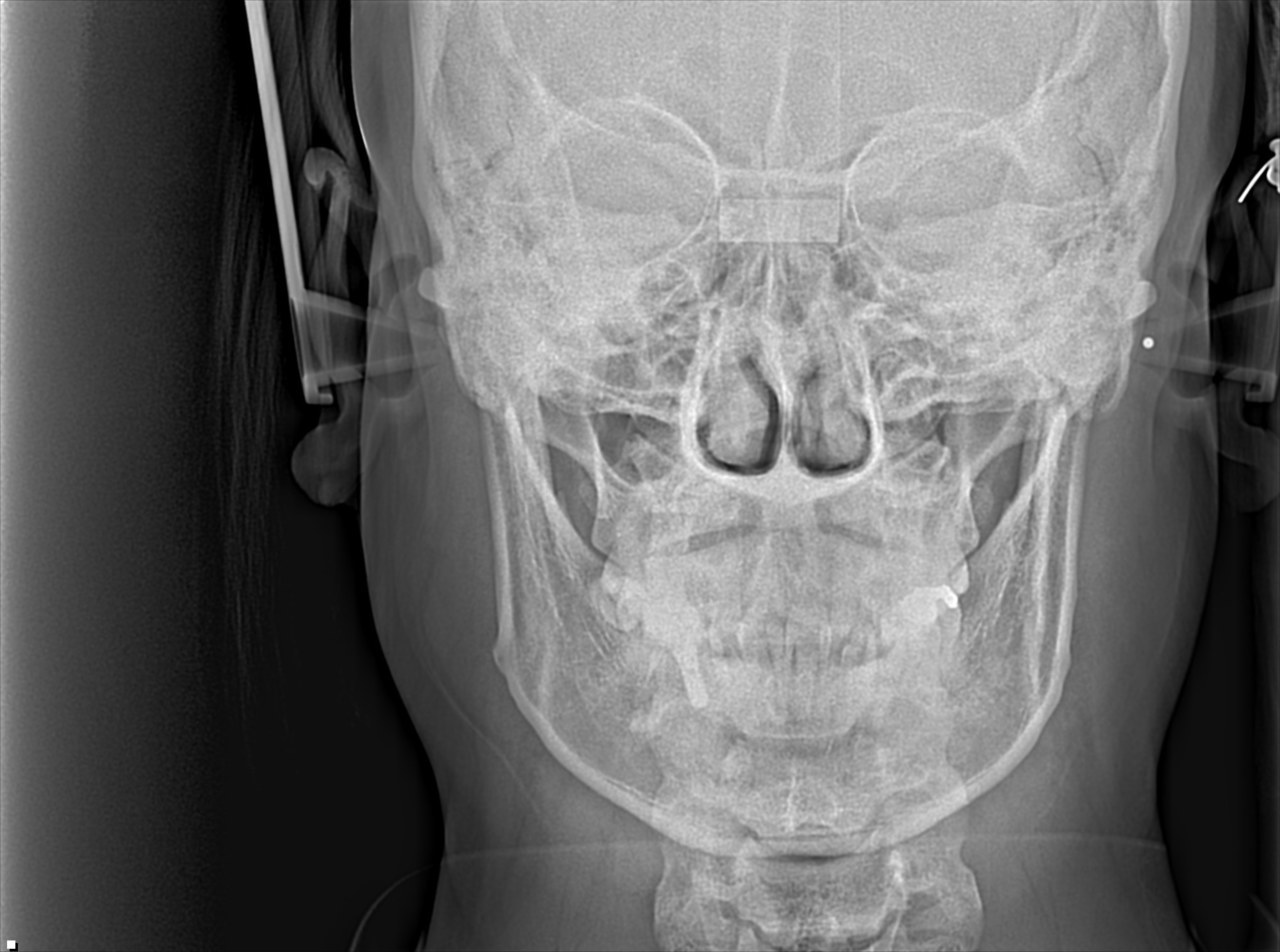

②セファロ

正面

セファロは矯正歯科特有のレントゲンです

正式には『頭部X線規格写真』といいます

撮影する条件が決まっており

名前にあるように『規格』化されています

そのため事前にレントゲン上で角度計測などを行い

歯列矯正後にその角度などを比較することもできます